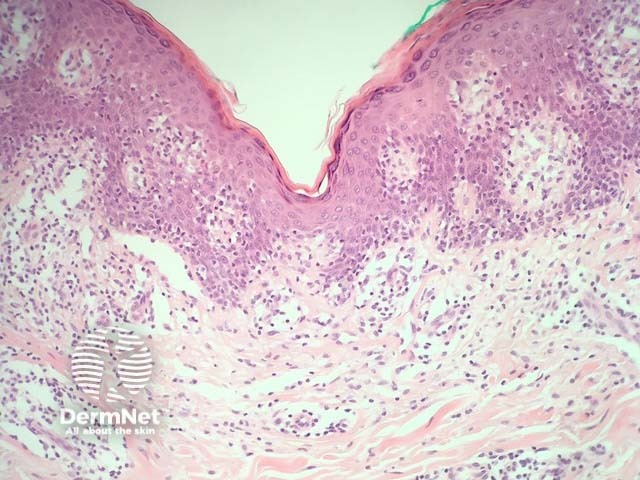

Patch stage mycosis fungoides: there is a superficial lichenoid infiltrate, mainly of lymphocytes and histiocytes and a few atypical cells infiltrating the epidermis without significant spongiosis (a phenomenon which is known as 'exocytosis', figure 1). This stage may be very subtle histopathologically and mimic other dermatoses such as eczema or lichenoid dermatoses, as the atypia may be difficult to appreciate. Often multiple biopsies are required to make the diagnosis and numerous studies may be needed to isolate or prove a clonal proliferation of T-cells.

Figure 1